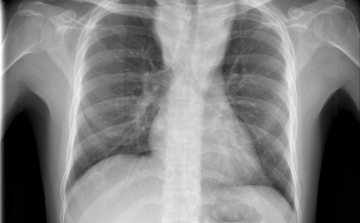

Terjed a tbc Szatymazon?

Hétfő reggel óta tbc-tesztet végeznek el a gyerekeken egy szatymazi általános iskolában, ahol egy hete fertőző tüdőbetegségben halt meg egy korábban ott dolgozó nő - közölték az M1 aktuális csatorna déli Híradójában.

Csökkent a tbc-fertőzések száma Európában

Átlagosan 4,3 százalékkal csökkent az új tuberkulózisos (tbc-s) esetek száma 2010 és 2014 között az Egészségügyi Világszervezet (WHO) 53 országot magába foglaló európai régiójában.